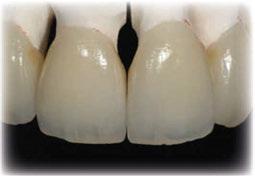

Terminada esta fase se elaboró una propuesta de diseño (CEREC,

SW 5.2, Dentsply Sirona) (Figuras 22-27), la cual fue materializada en dos tipos de materiales a partir de bloques cerámicos IPS Empress CAD y cerámica vítrea de disilicato de litio IPS E.max CAD (Figuras 28-30)

Respecto a materiales, las cerámicas vítreas reforzadas con leucita y disilicato de litio están diseñadas para ser utilizadas como medio aditivo para reemplazar estructura dentaria parcial o total perdida (11).

Las propiedades mecánicas de los materiales cerámicos de disilicato de litio presentan mayor

contenido cristalino, simulando las características ópticas de los dientes naturales, es así como en la revisión narrativa de Vichi y cols 2023 confirma sus propiedades y atributos de color como: luminosidad (amarillos/ azules, verdes/rojos), atributos geométricos como: opalescencia, fluorescencia, metamerismo y

brillo, coincidiendo con la dentición natural (12).

El tratamiento restaurador aditivo dentro de la rehabilitación oral completa puede ser un desafío clínico para el profesional. Este reporte de caso clínico demuestra que la fabricación de restauraciones indirectas CAD/CAM proporciona

estética y funcionalidad. Marchesi y cols 2021 determinaron las tendencias actuales de usos clínicos del material empleado en este caso en los dientes anteriores, al ser una cerámica feldespática reforzada con leucita presentando una fase vítrea (55% a 70%) convirtiéndose en uno de los materiales cerámicos más traslúcidos y estéticos usados para restauraciones adhesivas parciales con éxito y vida útil en la cavidad oral. Esto coincide con lo afirmado por Nejatidanesh et al 2018 (13) en su estudio retrospectivo sobre carillas con bloques Empress CAD, donde se evaluó el rendimiento clínico de las restauraciones preservando, en mayor cantidad, la estructura dental con tratamientos conservadores y resultados a largo plazo.